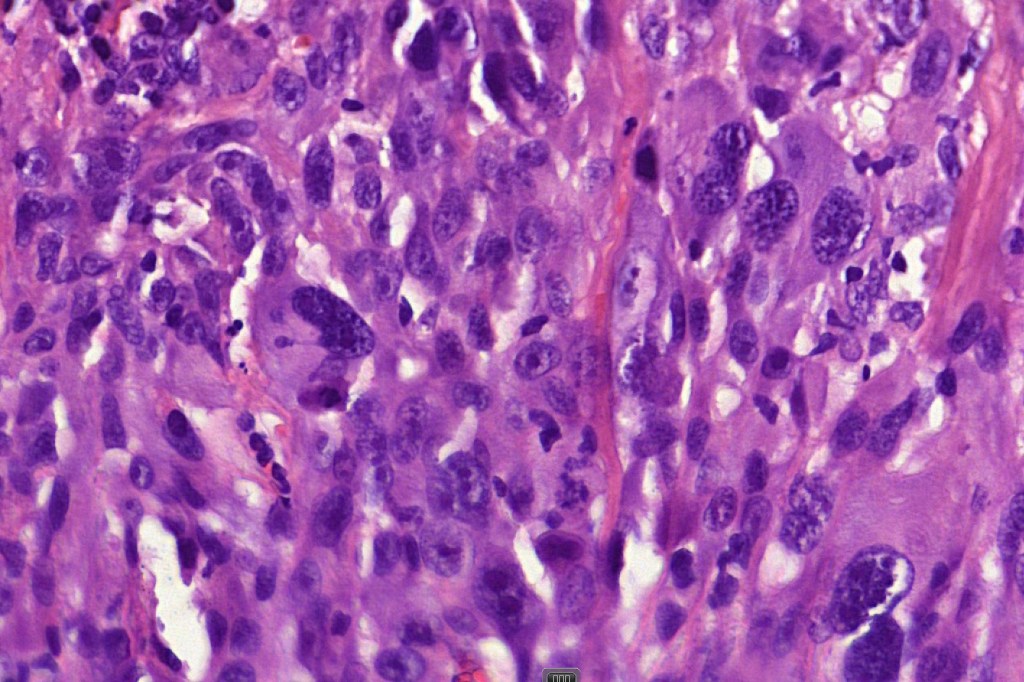

These are very rare variants of amelanotic or virtually amelanotic melanoma where a primary melanoma or a metastasis shows partial (DN) or complete loss (UN) of recognizable histological and immunohistochemical features. The histology may lead the pathologists to consider lymphoma, sarcoma, anaplastic carcinoma or a small cell tumor. Some examples of rhabdoid melanoma & melanoma with heterologous differentiation probably belong in this category. Ultimately, if there is no identifiable/recognizable primary tumor, diagnosis may only be comfortably made with next-generation sequencing. In the cases presented below, immunohistochemistry was of value in determining the melanoctic nature of the tumor (undifferentiated melanoma).